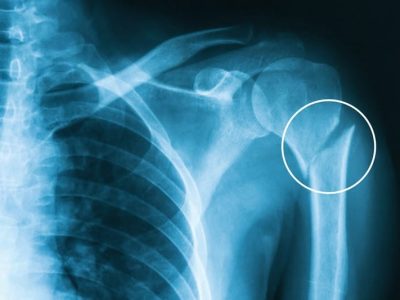

- Shoulder.

- Shoulder